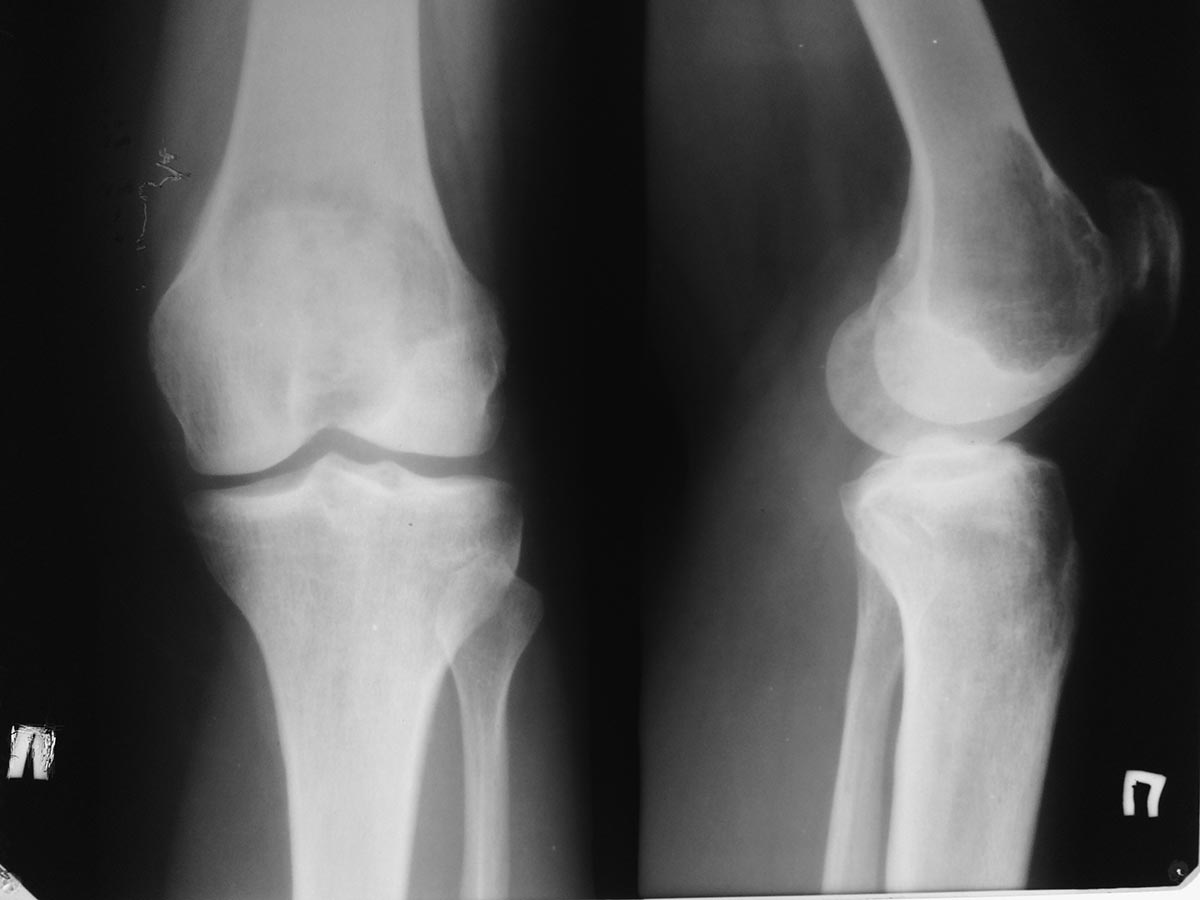

Помогите определиться с дальнейшей тактикой у молодой женщины с опухолью

дистального

отдела бедра.

Обратилась на консультацию молодая женщина 34 лет. В январе появилсь

боль в правом коленном суставе. Амбулаторно р- гр в прямой проекции -

норма. Была незначительная травма. Боль усилилась. На днях повторно

обратилась в поликлинику на рентгенограммах выявлена опухоль дистального

метаэпифиза бедренгой кости. Сделано мрт. Мягкотканного компонента нет.

Суставной хрящ пока интактен. Рентгенограмм прилагается. Завтра выложу

мрт и сделаем ркт (тоже выложу) Предполагаю, что это

остеобластокластома. Биопсию не сделаем, кт с контрастом

и сцинтиграфию тоже. Учитывая угрозу патологического перелома

рекомендовал костыли.